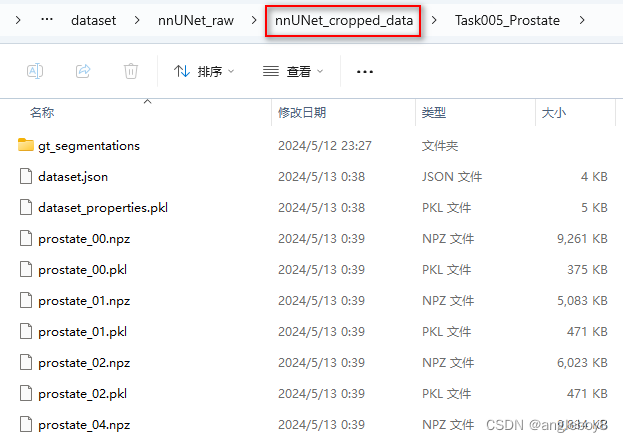

nnUNet_convert_decathlon_task -i 自己存放数据集的路径\Task05_Prostate运行结果目录如下:

以imagesTs为例:

按照官网进行数据预处理:

ValueError: need at least one array to concatenate”检测一下nnUNet_cropped_data是否生成了预处理的文件(*.npz和*.pkl):